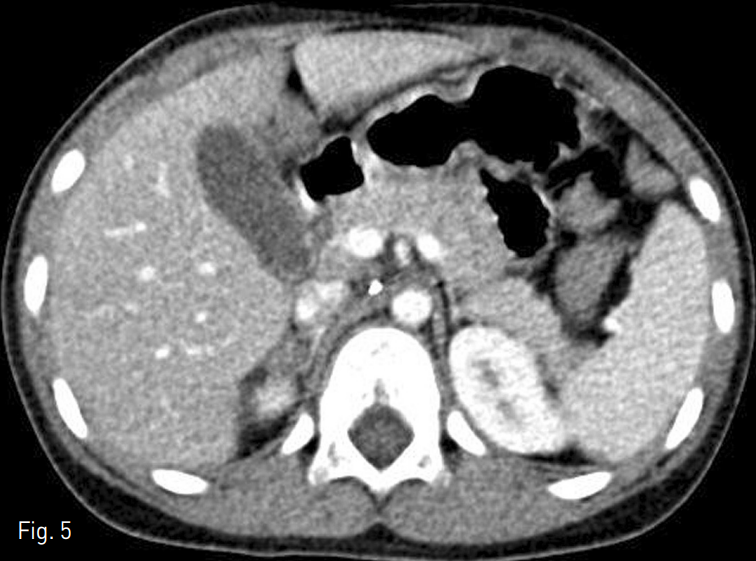

1개월 뒤 추적 복부 전산화단층촬영 상 오른쪽 부신경색과 함께 후복막 혈종의 감소 (Fig. 5) 를 확인할 수 있었고 환자는 시술 후 부신기능부전등의 합병증은 관찰되지 않았다.

Fig. 5

Follow-up CT obtained 1 month after embolization reveals decrease in amount of retroperitoneal hematoma with infarction of right adrenal gland.